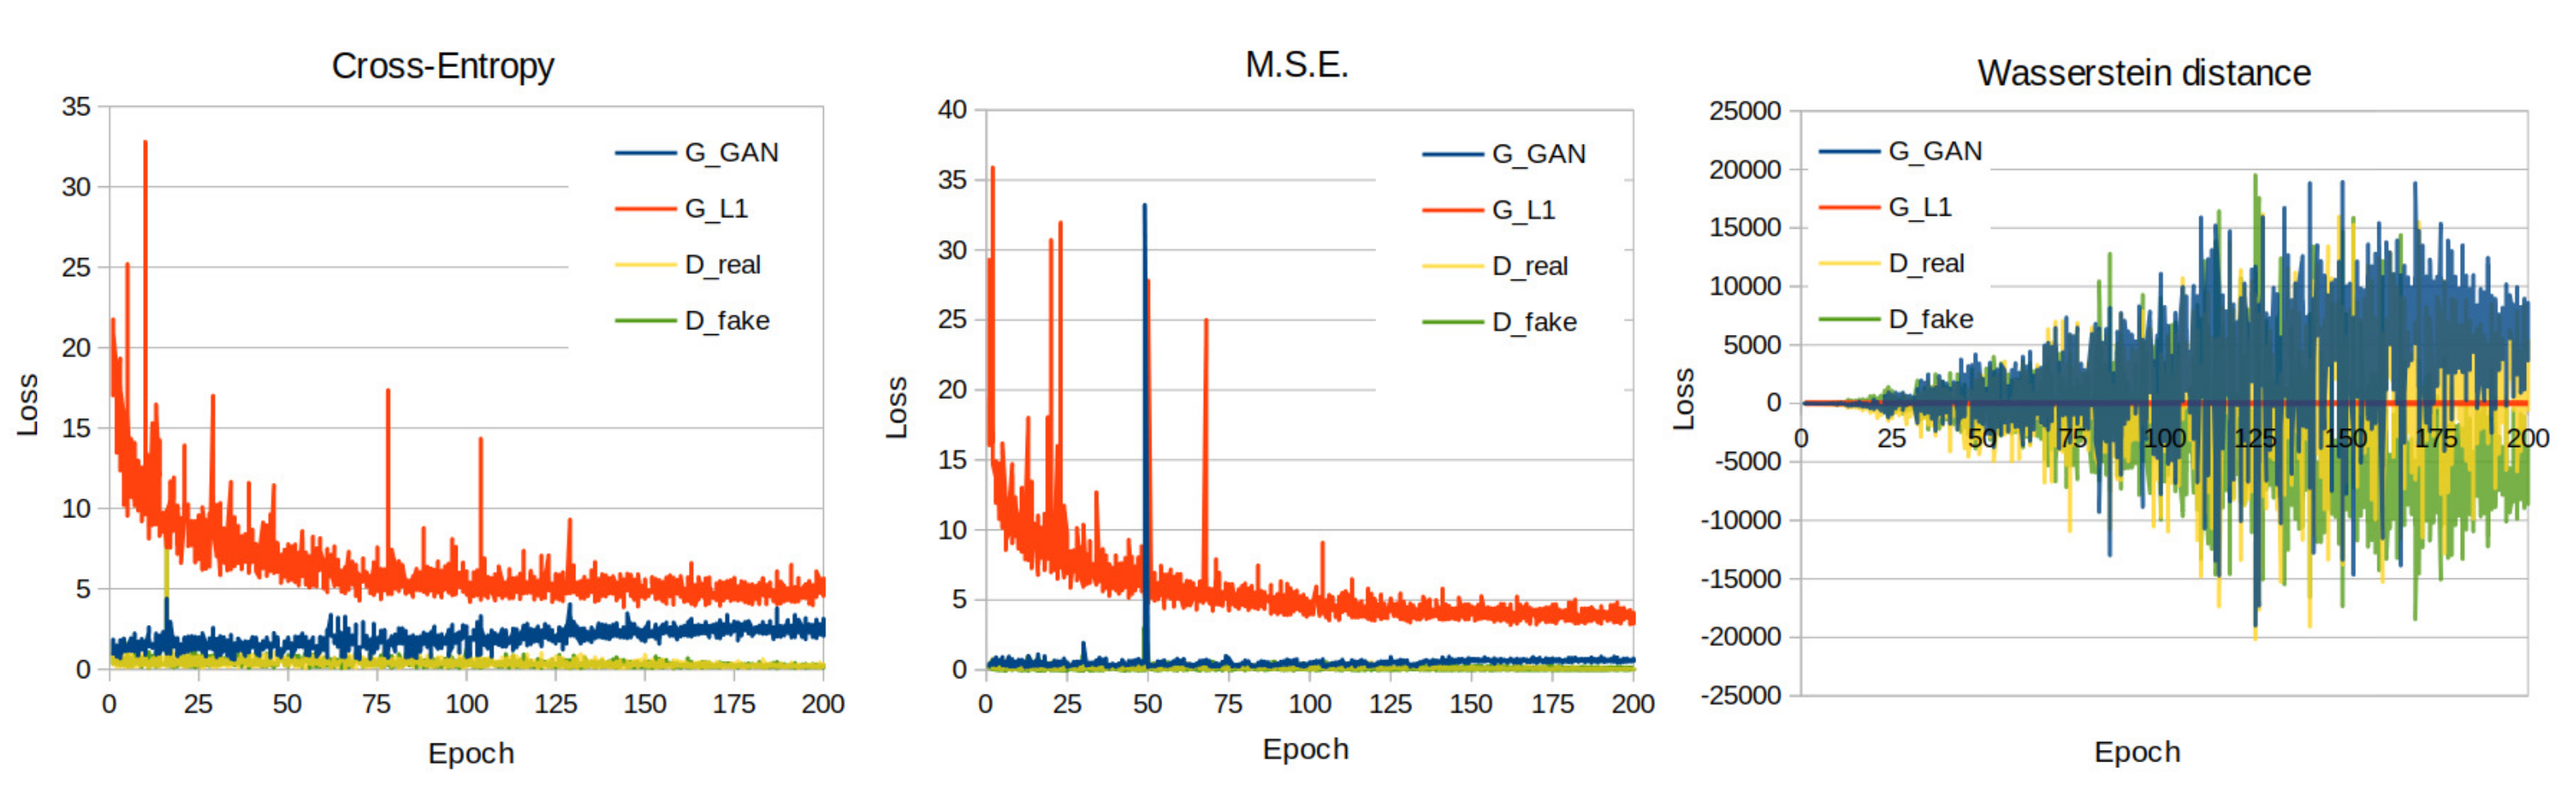

2.2. Modeling and Performance Evaluation

3. Results

3.1. Quantitative Evaluation